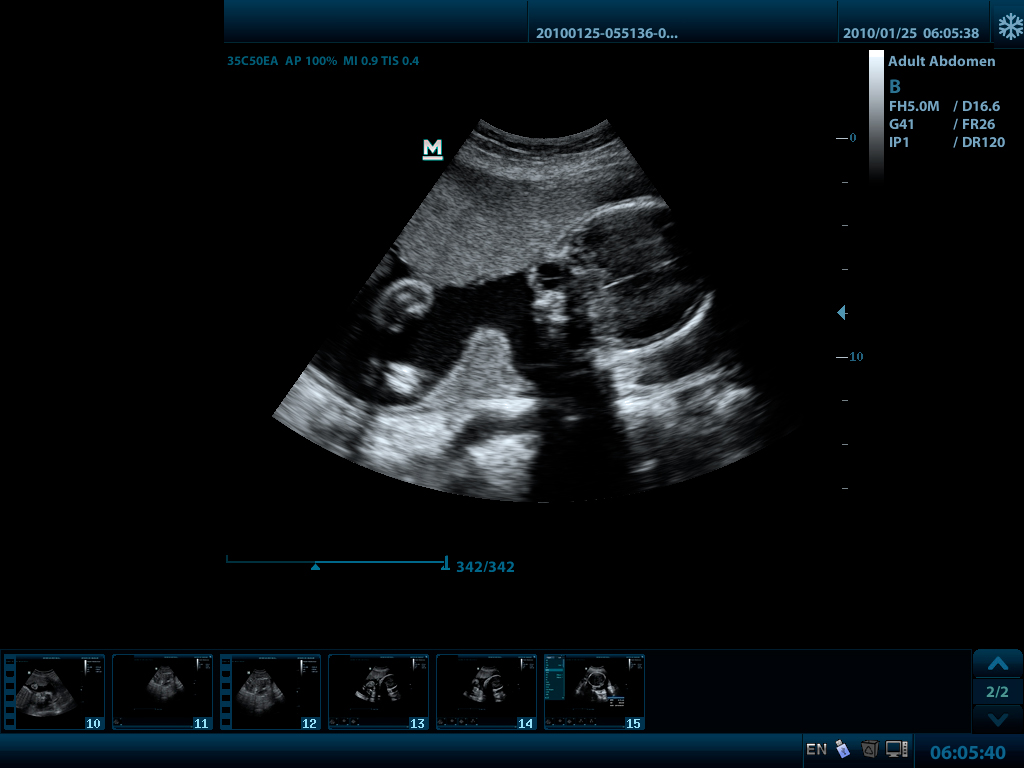

- Конвексный датчик 35C50EA, 1.7 - 6.0 МГц, радиус кривизны 50 мм